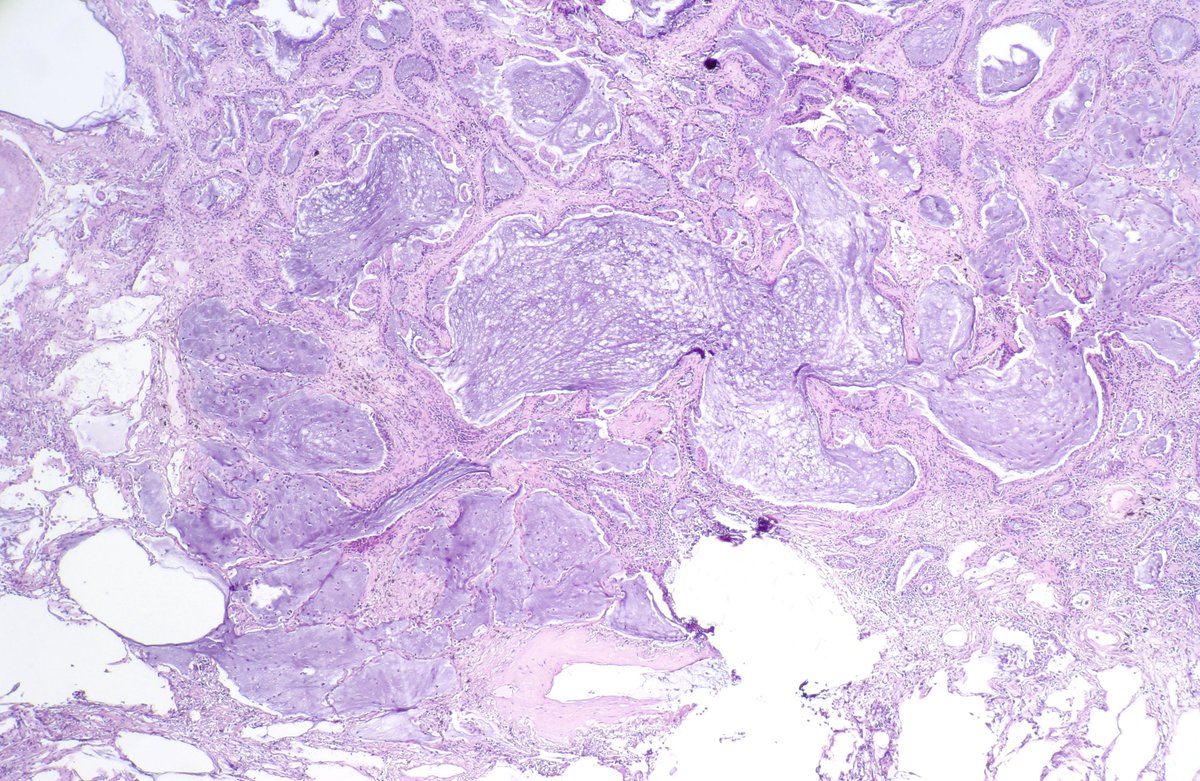

Type B2 Thymoma showing prominent large epithelial cells admixed with numerous lymphocytes. #pathology #PulmPath